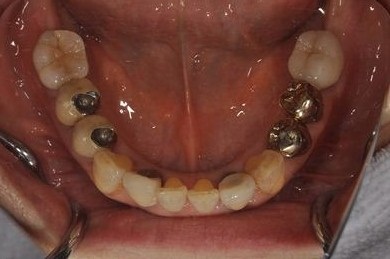

インプラントの症例写真 IMPLANT

| 治療内容 | インプラント8本(抜歯即日スピードインプラント、サイナスリフト)、ハイブリッドセラミック8本 | ||||||||||||||||||||||||||||||||

| 総治療費 | 3,495,050円 | ||||||||||||||||||||||||||||||||

| 治療期間 | 1年0ヶ月 |